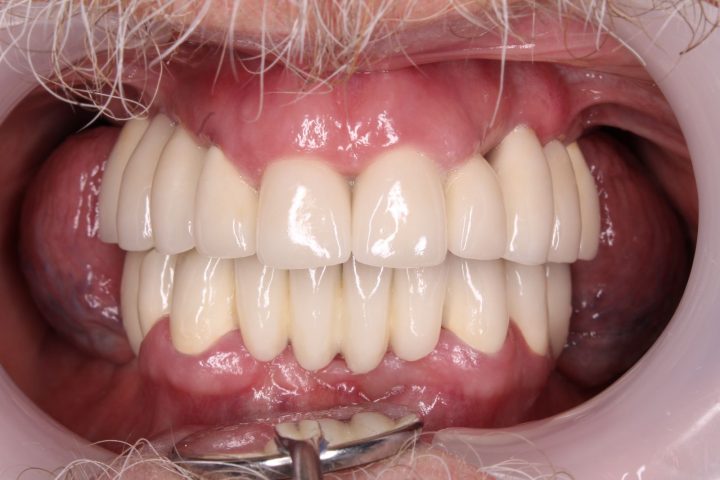

In der gleichen Behandlung hat er noch oben 4, und unten 6 Implantate bekommen, daneben hat er im Ablauf den 5 Tagen provisorischen Zahnersatz gekriegt.

Danach hatte er 4 Monate lange Heilungszeit, bald war den endgültigen Zahnersatz fertig: Oben wird eine Stegprothese auf 4 Implantate bearbeitet, unten wird eine Brücke auf 6 Implantate befestigt.